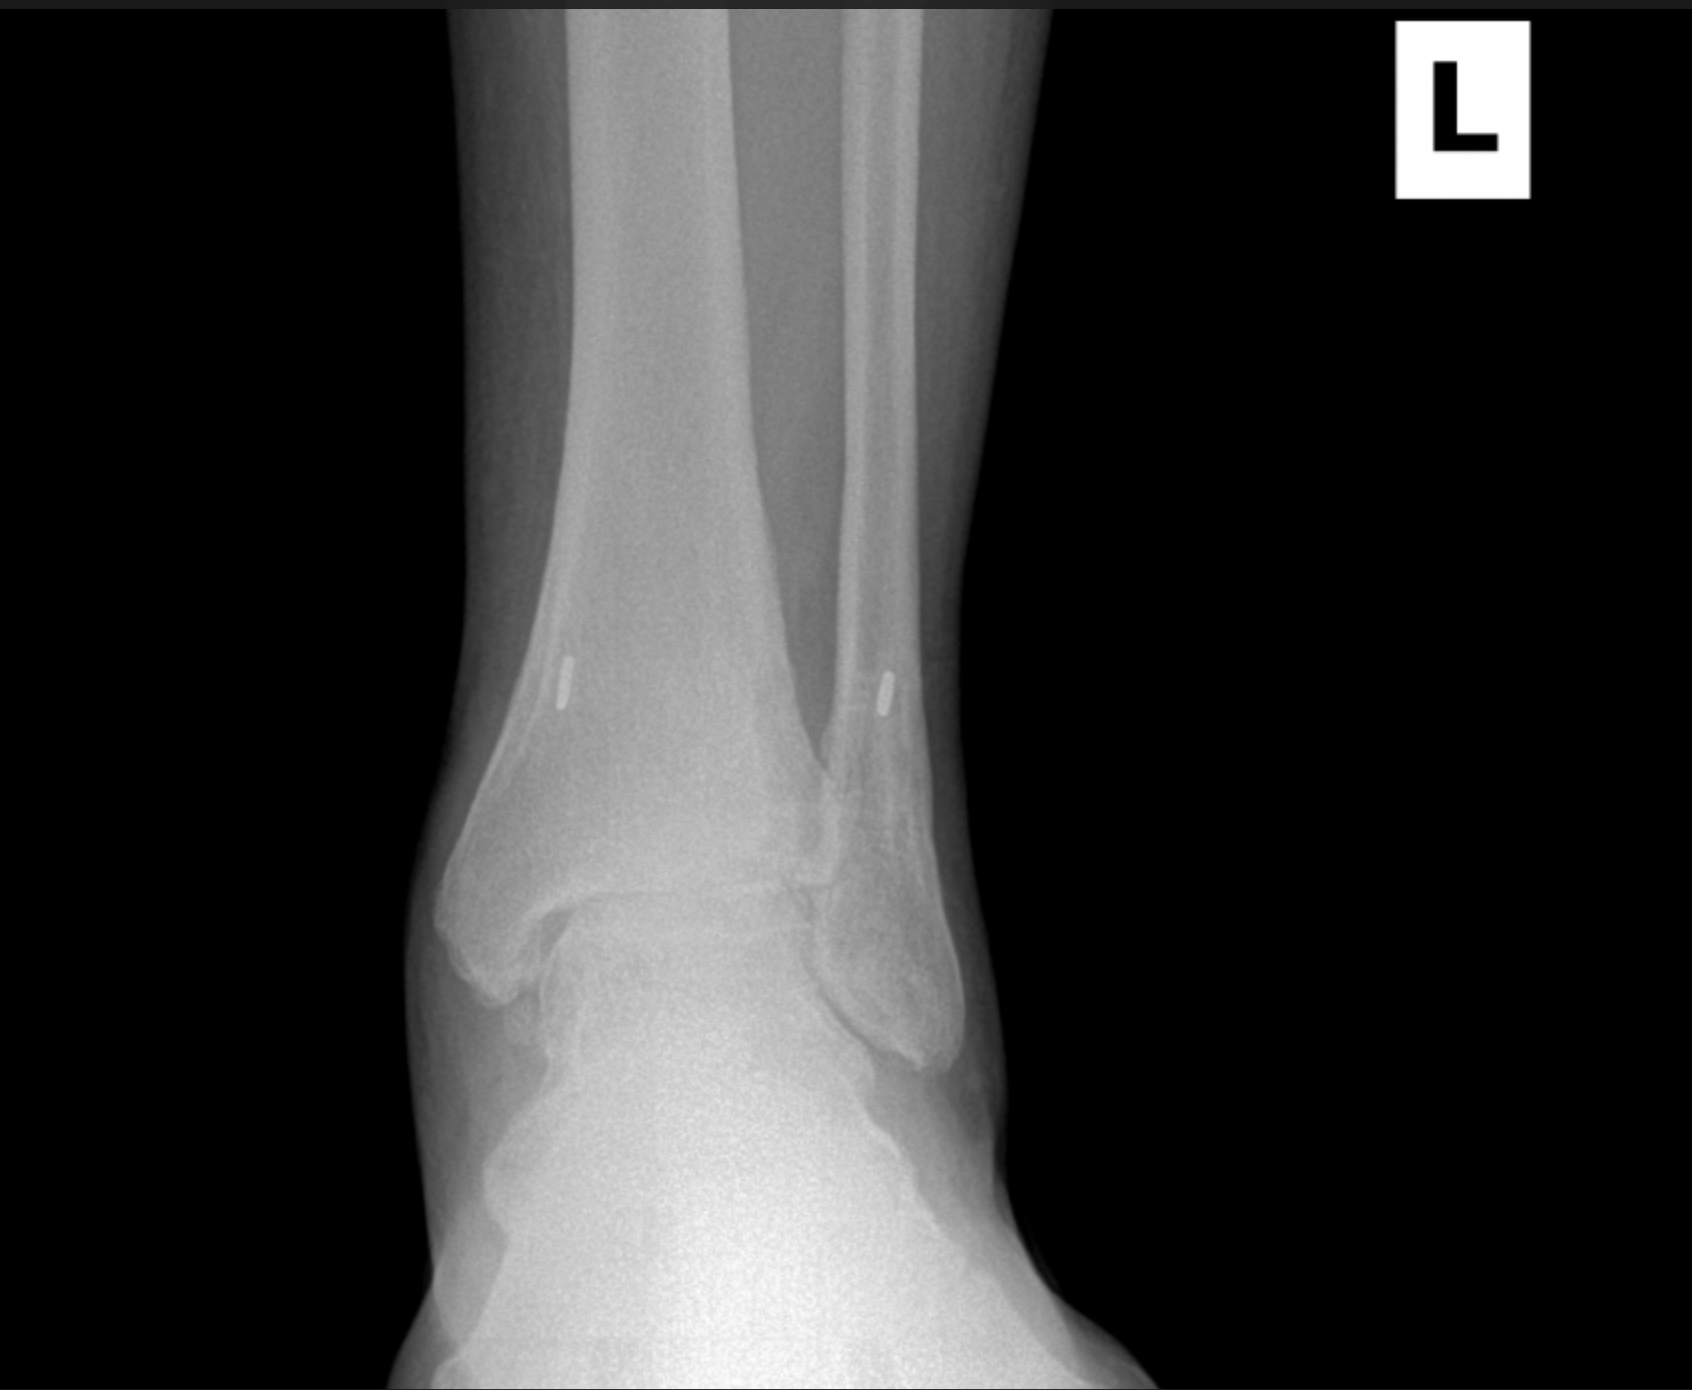

Foot & Ankle Replacement

Coming Soon